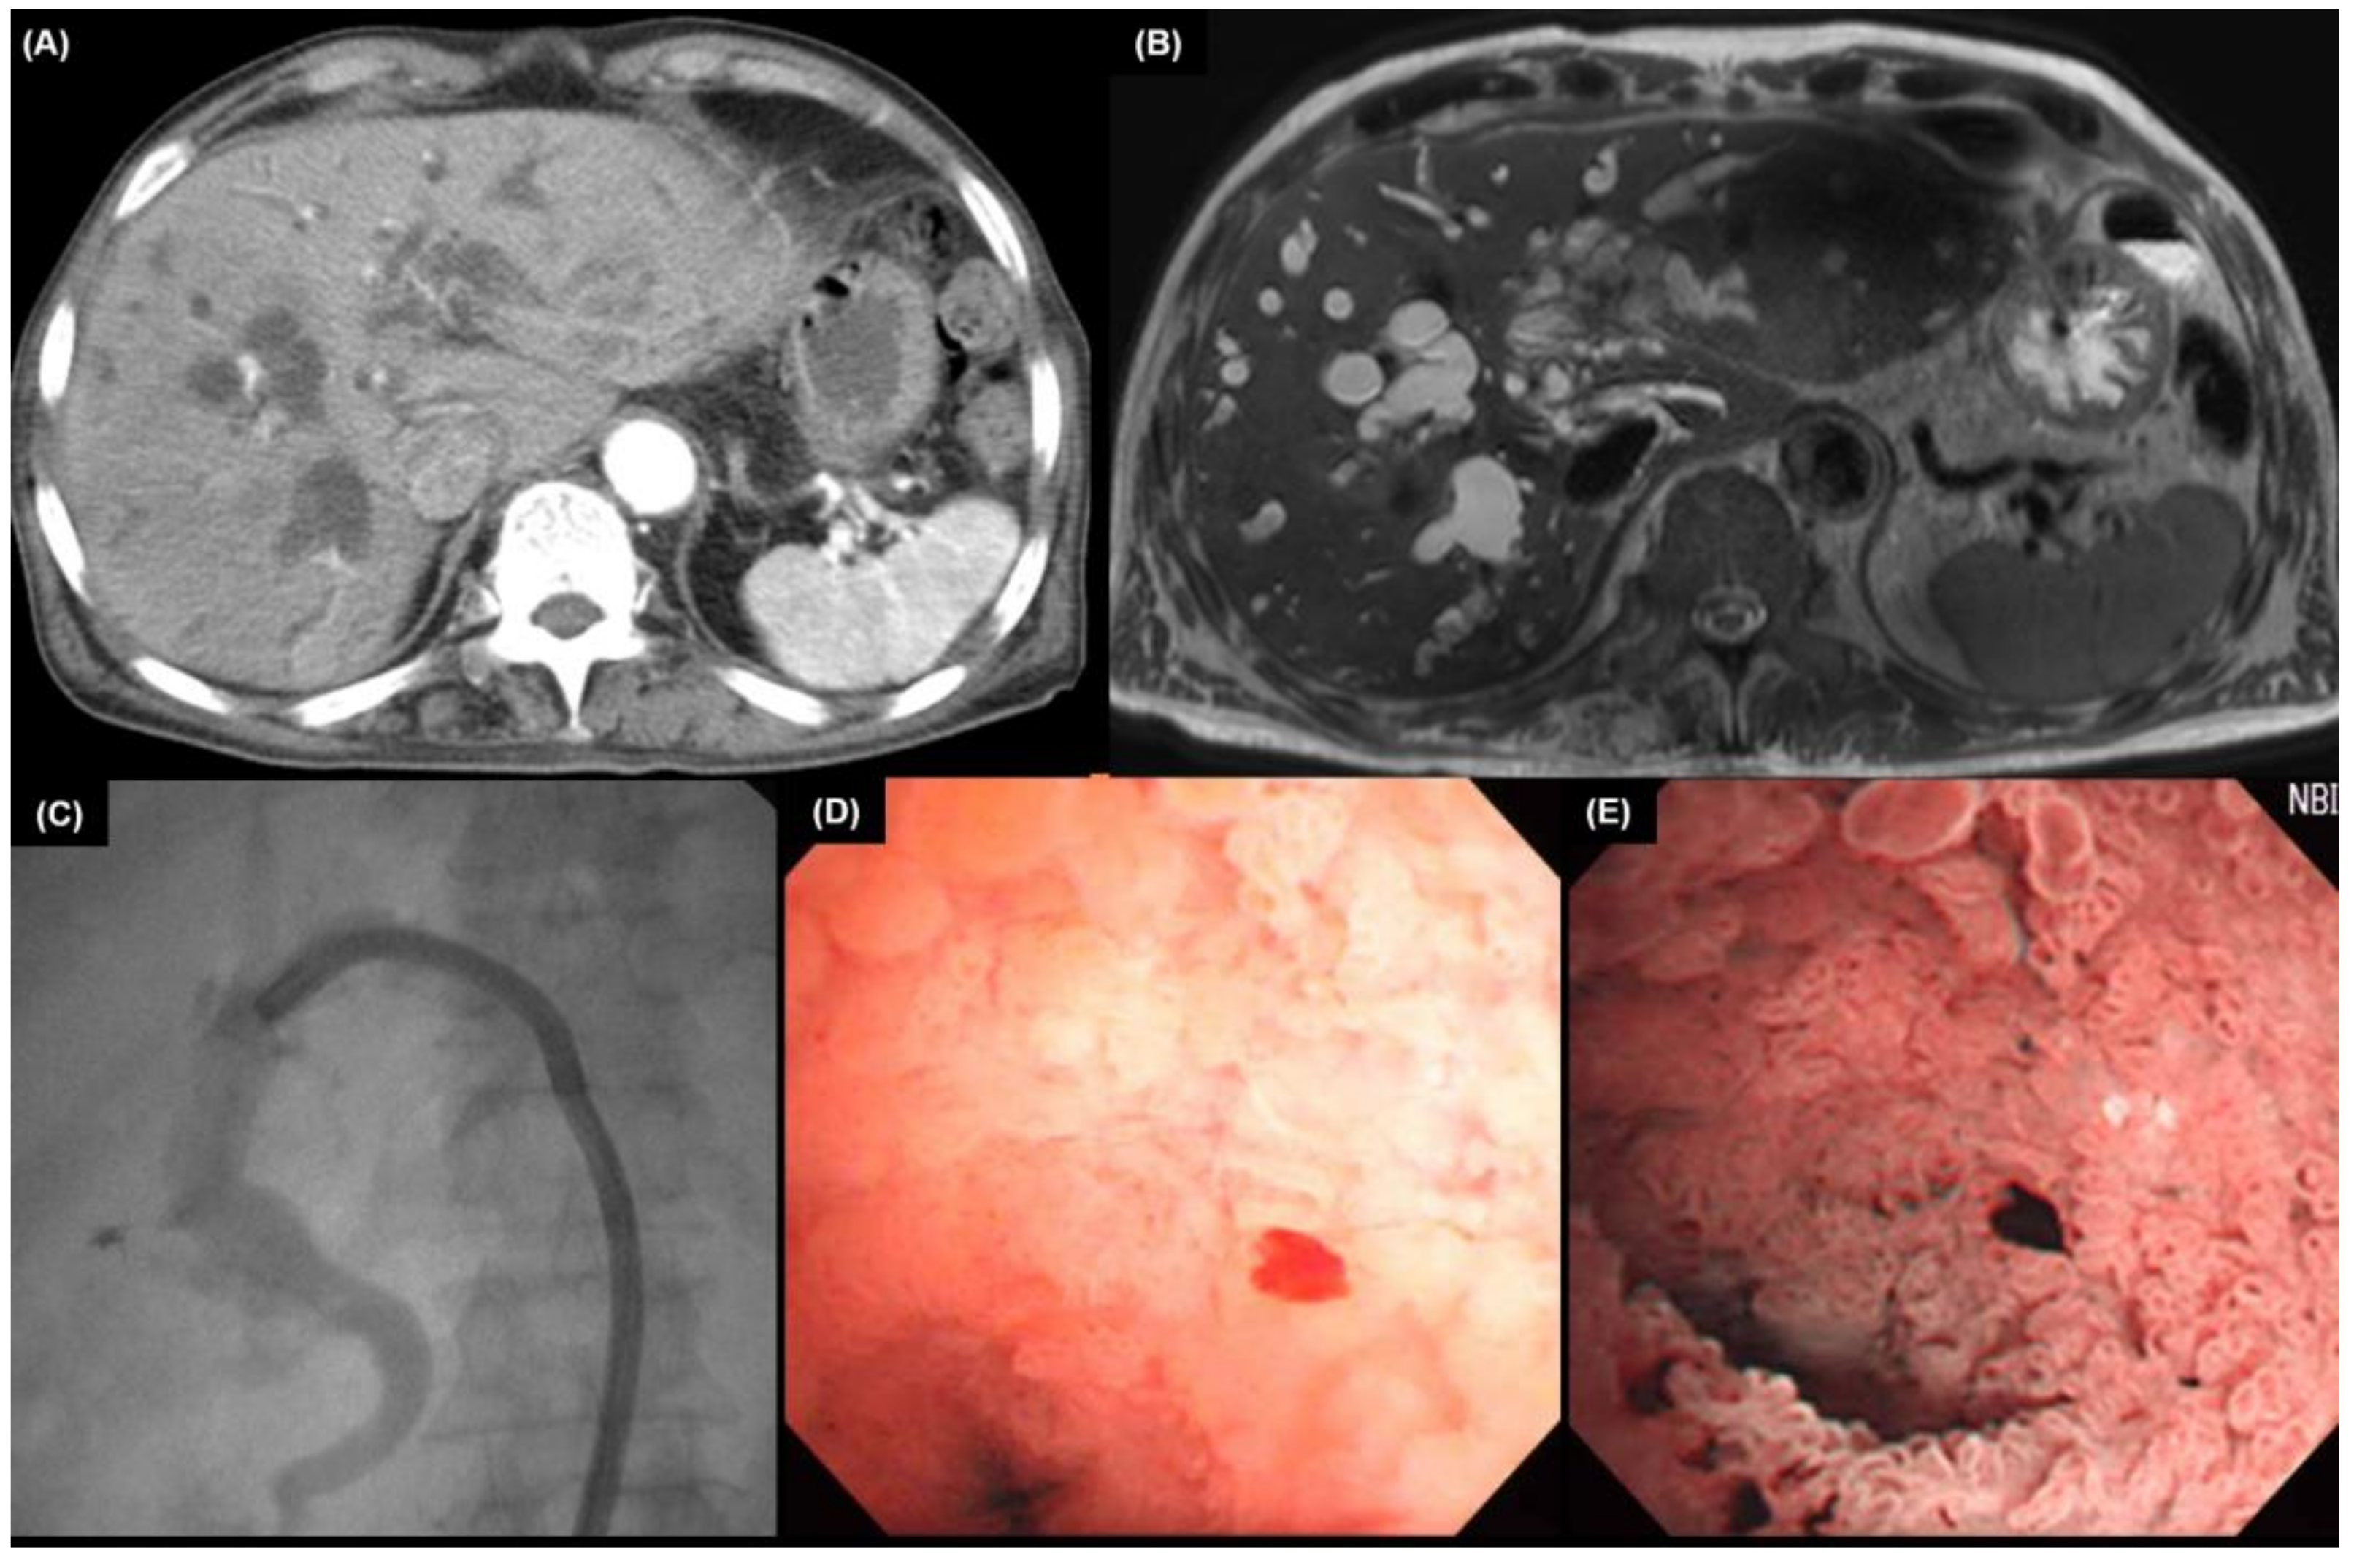

5.1. Cholangiography

5.2. Endoscopic Ultrasound

5.3. Intraductal Ultrasound

5.4. Cholangioscopy

6. Pathologic Findings